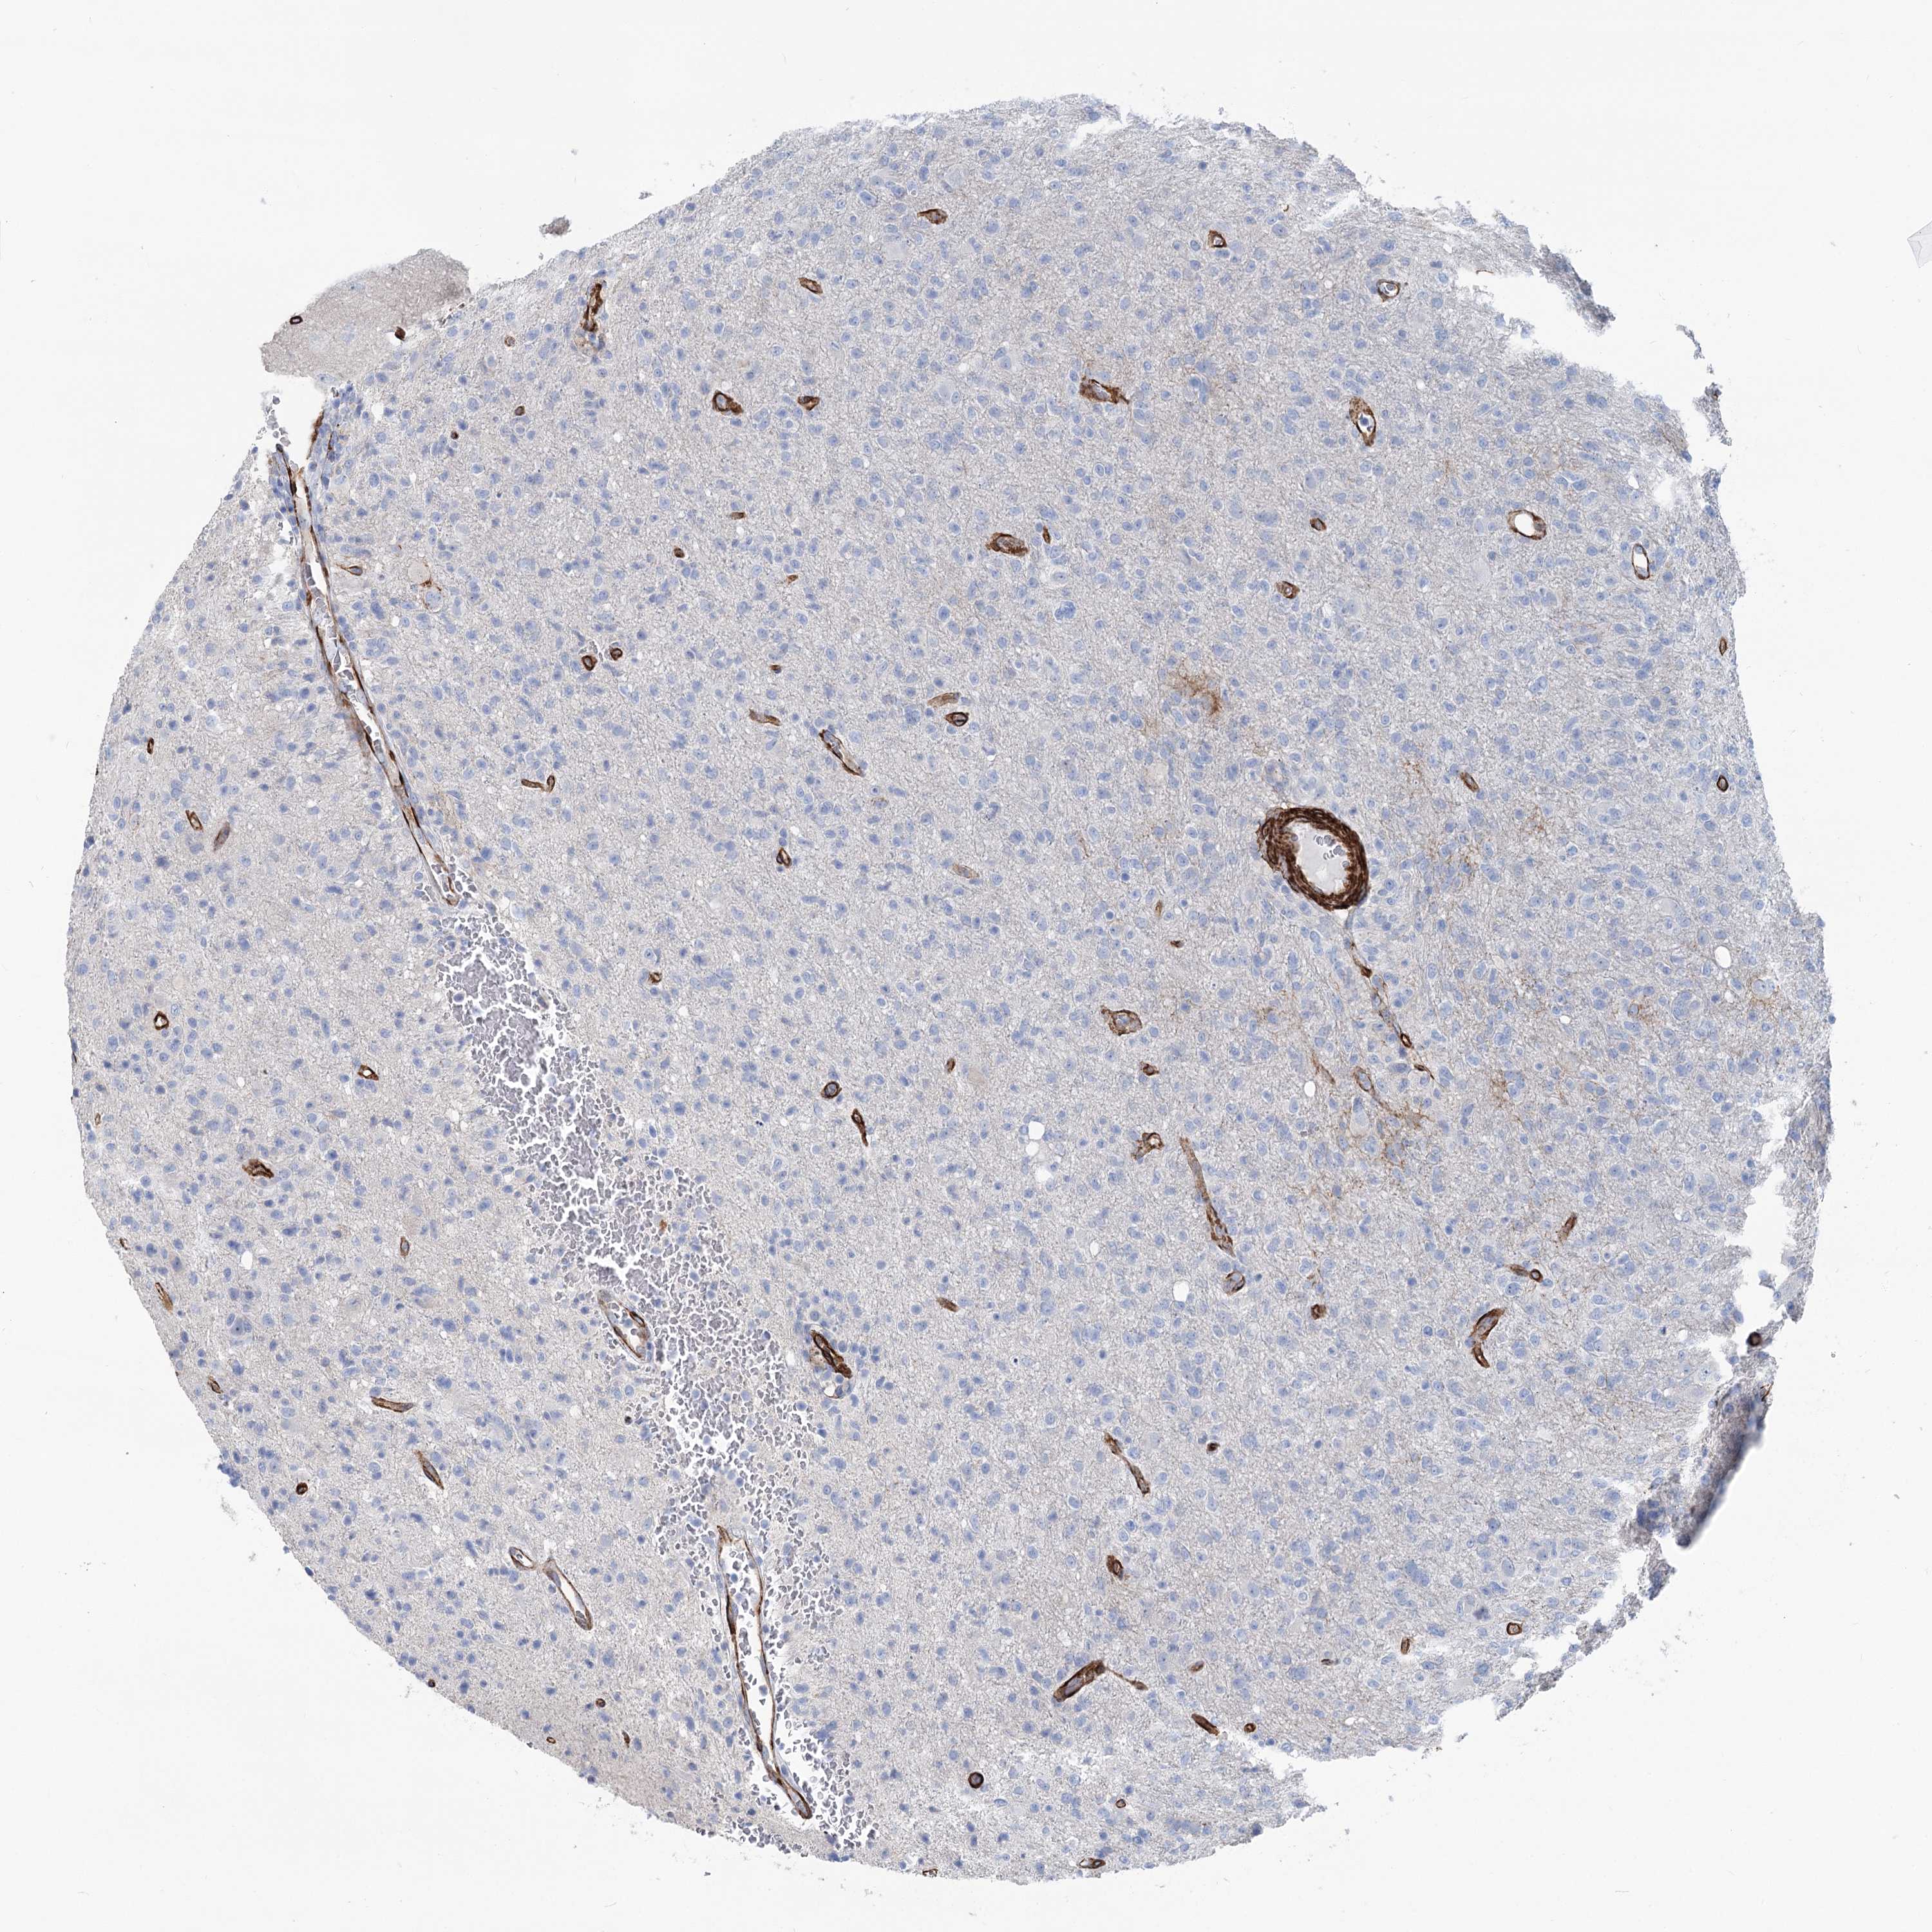

GLIOMA - Protein expressioni

A mouse-over function shows sample information and annotation data. Click on an image to view it in a full screen mode. Samples can be filtered based on level of antibody staining by selecting one or several of the following categories: high, medium, low and not detected. The assay and annotation is described here.

Note that samples used for immunohistochemistry by the Human Protein Atlas do not correspond to samples in the TCGA dataset.

Antibody stainingi

Antibody staining in the annotated cell types in the current human tissue is reported as not detected, low, medium, or high, based on conventional immunohistochemistry profiling in selected tissues. This score is based on the combination of the staining intensity and fraction of stained cells.

Each image is clickable and will lead to virtual microscopy that enables deeper exploration of all samples and also displays staining intensity scores, fraction scores and subcellular localization as well as patient and tissue information for each sample.

Antibody HPA038143

Antibody HPA038144

Staining

High

Medium

Low

Not detected

Intensity

Strong

Moderate

Weak

Negative

Quantity

>75%

75%-25%

<25%

None

Location

Nuclear

Cytoplasmic/membranous

Cytoplasmic/membranous,nuclear

Glioma, malignant, High grade

Glioma, malignant, Low grade

Glioblastoma, NOS